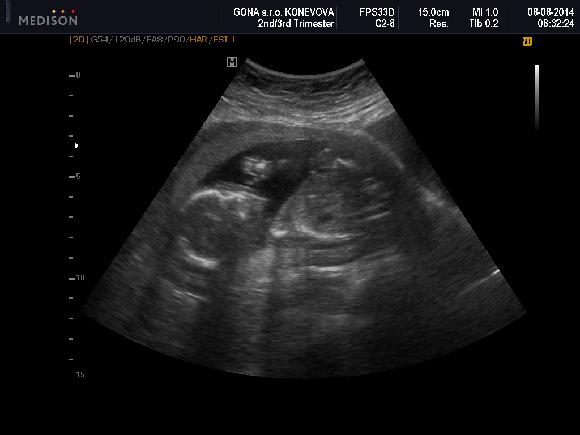

Tak ještě sem dám fotku našeho miminka-jak ukazuje dlouhý nos. To dítě bude mít smysl pro humor

Ahoj holky,tak se hlásím z včerejšího velkýho utz,dneska jsme 21+0 všechno v pořádku,tak teď už si to budeme jen užívat :-) Teď vyřázíme ke švagrové,ta čeká prcka v září,tak budeme mít v rodině veselo :-) Přikládám vám foto :-) Jinak Gilmorovi děvčata taky můžu,ale teď co jsem doma tak čumím v televizi snad na všechno :-)